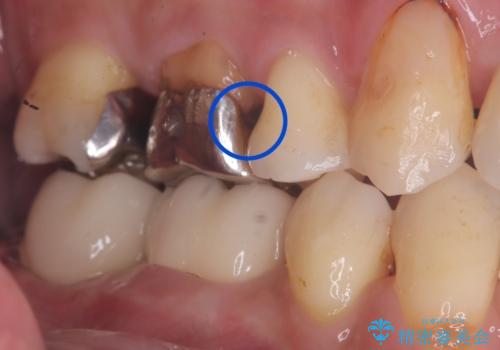

メタルインレーを除去したところう窩が深く、遠心の健歯質が歯肉縁下深くに位置したためディスタルウェッジ術を行い骨と歯肉の高さを下げた上で補綴しています。

元々インレーが入っていましたが、残存歯質量が少なく破折のリスクを説明しジルコニアクラウンでのやり替えとなりました。